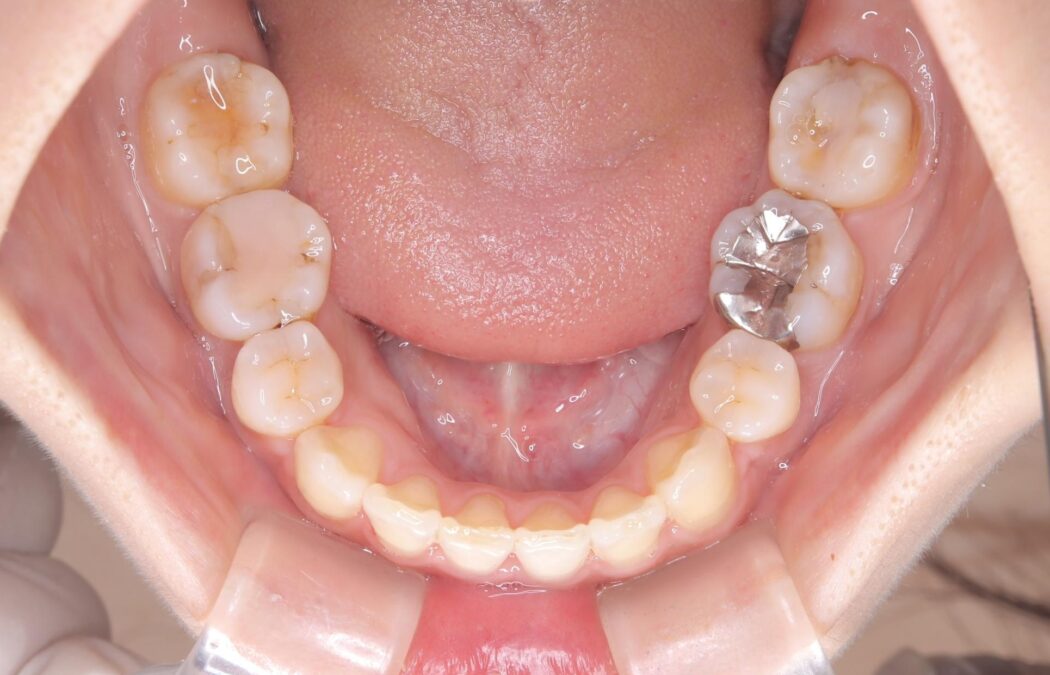

口元を下げて前突感を無くしたい、下の歯の凹凸も無くしたいとご来院された患者様です。

アゴの骨格的なズレがあったため、歯の真ん中を完全に合わせることは不可能と説明。上下4本抜歯を行い、ワイヤー矯正で噛み合わせの大きな改善を目指しました。